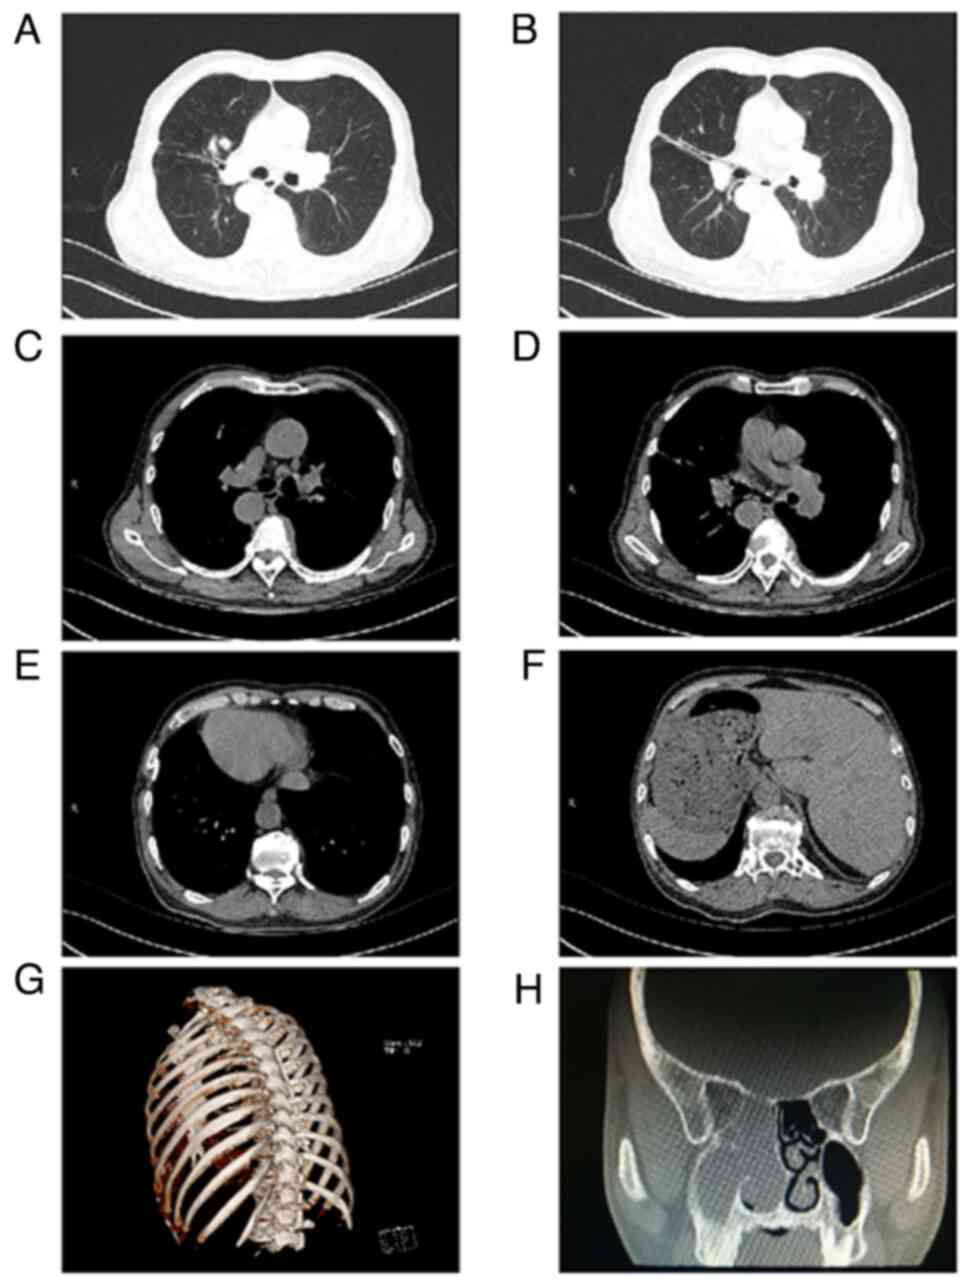

Kartagener syndrome combined with small cell lung cancer: A case report and literature review

Kartagener syndrome (KS) is a rare autosomal recessive genetic disease characterized by visceral inversion, sinusitis and bronchiectasis. Small‑cell lung cancer, a common tumor with poor prognosis, rarely coexists with KS. The lack of typical clinical symptoms can lead to missed or incorrect diagnoses, and to date, only few cases of this combination have been reported. The current study presents a case of KS with small cell lung cancer that was promptly diagnosed and treated at Jining No. 1 People's Hospital (Jining, China). Sharing this case may contribute to the advancement of respiratory medicine and aid doctors in the diagnosis and management of similar conditions.

Figure 1